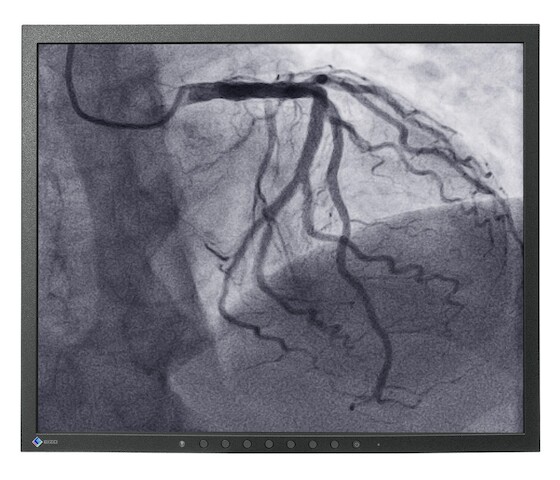

19-Zoll OP-Monitor für die präzise Darstellung und Diagnose von Bildern.